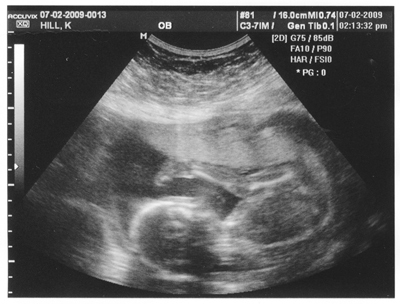

Baby Hill is a girl. And I have the pictures to prove it.

But our little girl was practically doing somersaults while the ultrasound technician was checking her over so it was easy to get a clear view.

“It’s a girl,” she said … dang it, I should’ve gotten the name of the technician.

Knowing that we would be telling quite a few people this news, I asked the technician again if she was sure it’s a girl, and she said, “I’m sure.”

Later I looked at the ultrasound images the technician printed up and saw that she had labeled one of them “girl” so we could examine more closely. I had read up on how technicians can tell the sex of the baby so when I got a good look at it over the weekend I could see why she was so sure.

As far as planning goes, we would like to get some input on names, so look online soon for a baby-name contest at northwest-2.carpentermediagroup.com/covingtonreporter and www.maplevalleyreporter.com. You can see two ultrasound images from July 2 online.